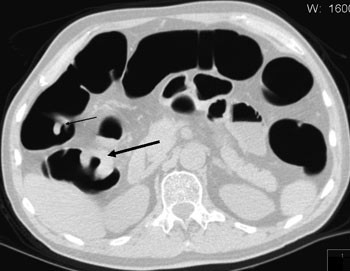

Den største og så langt mest positive publikasjonen inkluderte 1 233 personer med middels risiko for kolorektal kreftsykdom og som fikk utført CT-kolografi som screening (9) (fig 1). Det ble benyttet et tømmingsregime med fosforalløsning, manuell innblåsning av romluft, fekal merking, multidetektor-CT og gransking primært med tredimensjonal virtuell koloskopi utført av erfarne radiologer. Sensitivitet per pasient for adenomatøse polypper ≥ 8 mm var 94 %. 55 polypper ≥ 5 mm ble påvist av kun CT-kolografi primært og verifisert først ved annen gangs koloskopi. De fleste av disse var lokalisert bak en tarmfold eller nær anus. Totalt sett var det ingen signifikant forskjell i sensitivitet mellom CT-kolografi og koloskopi for adenomatøse polypper ≥ 8 mm. To av polyppene var maligne. CT-kolografi påviste begge, mens en 11 mm stor malign polypp ble oversett ved første gangs koloskopi. For såkalte flate adenomer isolert sett var sensitiviteten ved CT-kolografi 80 %. Pasienttiden ved CT-kolografi var i gjennomsnitt 14,1 minutter og ved koloskopi 31,5 minutter.

CT-kolografi synes å være spesielt godt egnet etter inkomplett koloskopi, helst utført samme dag. Pasienten vil i så fall allerede være forhåndstømt og ha en del gass i tykktarmen. Merbelastningen ved en CT-kolografi vil i så måte være beskjeden. I et materiale på 40 ufullstendige koloskopier ble det rapportert at CT-kolografi gav en fullstendig fremstilling av tykktarmen i over 90 % av tilfellene (31). Egne erfaringer som er gjort på denne type problemstilling, er også positive (fig 2). Når koloskopi er ufullstendig på grunn av strikturerende cancer, vil det kunne være hensiktsmessig at den supplerende CT-kolografiundersøkelsen utføres med tilpasset stråledose og intravenøs kontrast for eventuelt å påvise metastaser til lever og abdominale lymfeknuter.